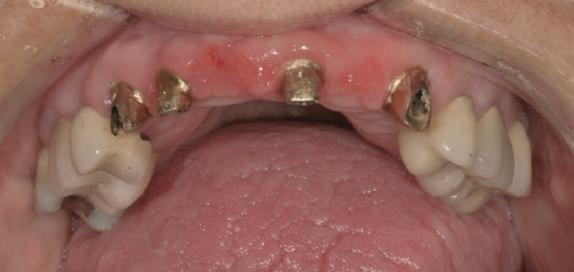

Cazul (6)

Submergenţa radiculară

Acest pacient s-a prezentat cu o punte 1.3.-2.3. compromisă.

Pentru a păstra limitele restaurării fixe pe toată durata tratamentului, s-au inserat în primă etapă implanturi corespunzător 1.3. şi 2.3. După integrarea acestora, s-au aplicat bonturi individualizate, iar restaurarea provizorie s-a rebazat pentru suplimentarea suportului.

Implanturile şi bonturile ulterioare aferente s-au putut poziţiona în poziţiile 1.2. şi 2.1. Incisivul 1.1. a beneficiat de tratament endodontic electiv pentru a fi redus şi în cele din urmă, după inserarea bonturilor pe implanturile 1.2. şi 2.1., a fost scufundat (fig. 20, 21).

Atitudine: În fig. 21, este evident că, după submersiunea radiculară, nu se

obiectivează recesie în jurul bonturilor 1.2. şi 2.1. De notat osul excelent vestibular în dreptul tuturor implanturilor, fără recesie în jurul 1.3. şi 2.3. (fig. 22) care au fost inserate cu 8 luni înainte de 1.2. şi 2.1. Perioada scursă între scufundarea rădăcinii (fig. 20) şi inserarea punţii finale (fig. 22) a fost de 7 luni (fig. 23).

Figurile

20. Dintele 1.1. tratat endodontic.

21. Dintele 1.1. submersat în cele din urmă după inserarea bontului la nivel 1.2. şi 2.1.

22. Os excelent vestibular faţă de toate implanturile; nicio recesie la nivelul 1.3. şi 2.3. 23. Punte provizorie pe toate bonturile.